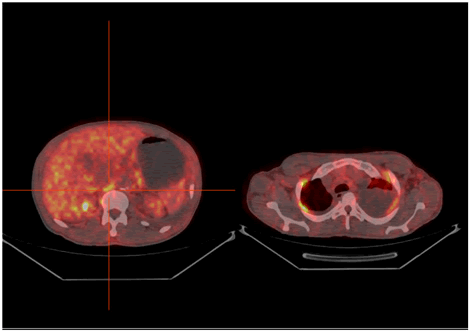

PET–CT with 18F-FDG was performed showing physiological uptake of 18F-FDG in the 3D Maximum Intensity Projection (3D MIP) (Figure 1), and unhabitual diffuse and stepped hypermetabolism interesting intercostals muscles and diaphragm in (3D MIP) and Fused PET/CT images in axial sections (Figure 2), this exceptional uptake was explained by the breathing difficulties relating to dyspnea. In addition to this finding, multiples pleural, pericardial and abdominal effusions without hypermetabolism, were observed in the context of hydrops. We report in our exploration the total disappearance of the pathological lymph nodes hypermetabolism previously described in the intermediary PET-CT, evoking a complete metabolic response.

Figure 2. Fused PET/CT images in axial sections showing corresponding high intensity uptake within right diaphragm and intercostal muscles.